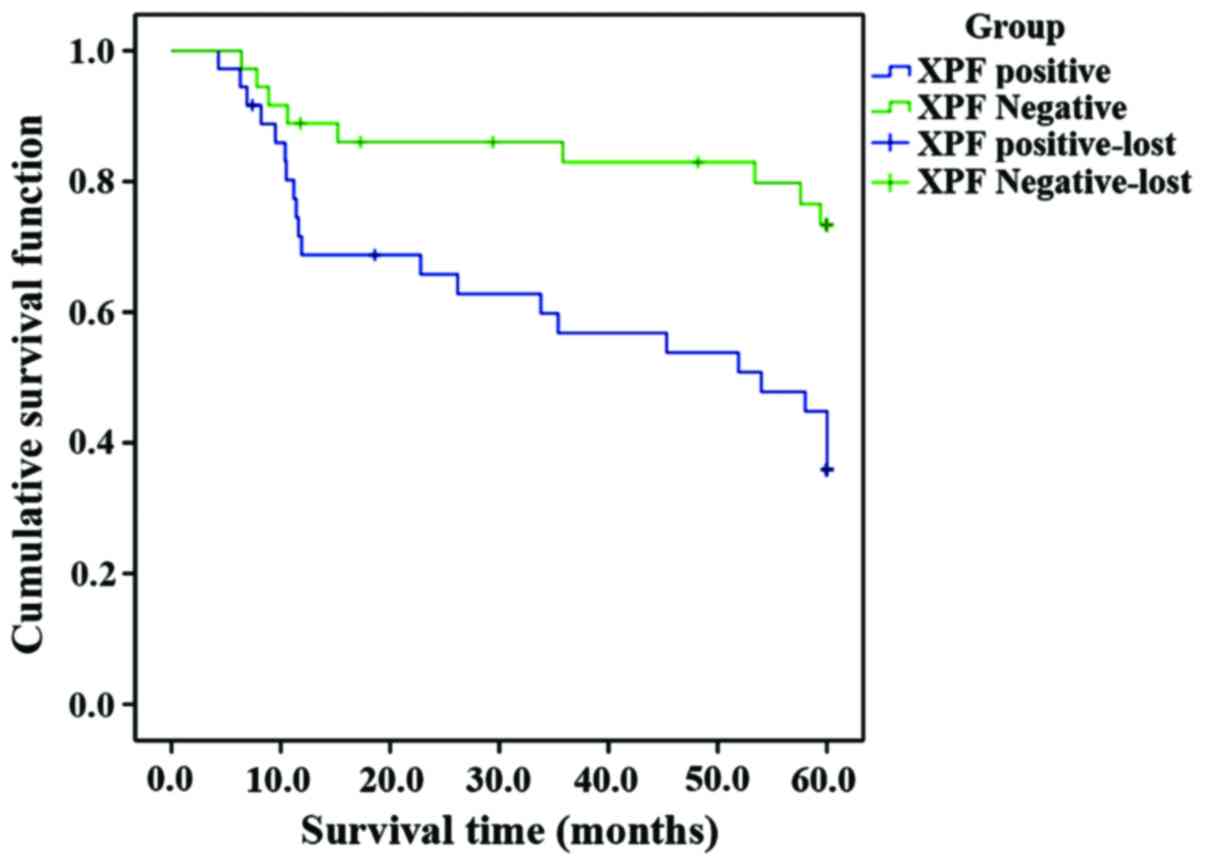

Kaplan-Meier survival analysis showed that the

survival time of XPF-positive patients was shorter than that of

XPF-negative patients. Inspection results using 3 different

statistics were basically the same, and the differences were

statistically significant (P<0.05) (Fig. 2 and Table

V).

Association between XPF expression and prognosis of

gastric cancer. Currently, exact pathogenesis of gastric cancer has

not been fully clarified; but many studies have shown that repair

gene is not only correlated with the occurrence and development of

gastric cancer, but also closely associated with the prognosis

(20). In this study, we performed

survival analysis for XPF-positive and -negative patients with

gastric cancer, and the results showed that the survival time of

XPF-negative patients was longer than that of XPF-positive patients

(P<0.05); we selected clinicopathological indexes according to

the prognostic factors of gastric cancer patients, performed

regression analysis using Cox's hazards model, and results

suggested that XPF was an independent prognostic factor. This

suggested that positive expression of XPF gene, in addition to its

critical effect on the formation of gastric cancer, exerts a larger

effect on the distant metastasis or recurrence of tumor in the

progressive stage. Thus, XPF can serve as an important index

affecting the prognosis of gastric cancer patients (21).